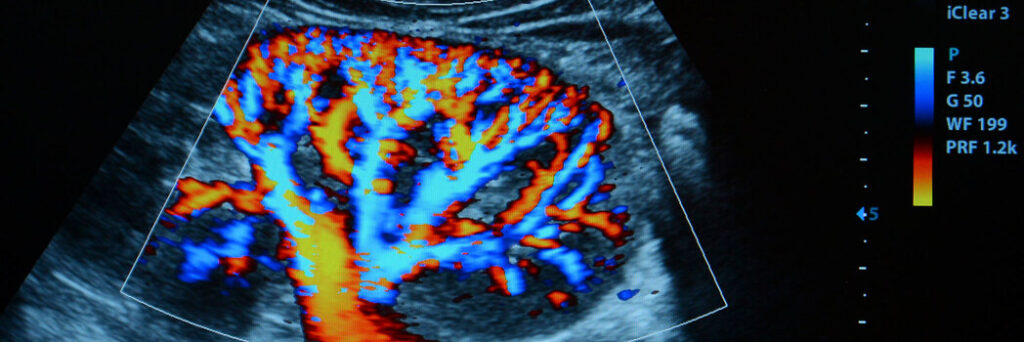

O Doppler colorido é um tipo de ultrassonografia vascular que utiliza ondas sonoras de alta frequência para mostrar o fluxo sanguíneo em artérias e veias. Diferente do ultrassom convencional, o Doppler não apenas mostra imagens das estruturas anatômicas, mas também avalia a velocidade e a direção do sangue que circula nos vasos.

As áreas com bom fluxo aparecem em cores diferentes na tela, geralmente vermelho e azul, facilitando a análise de possíveis obstruções, refluxos ou alterações no padrão circulatório.